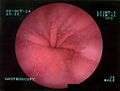

Upper GI endoscopy depicting hiatus hernia